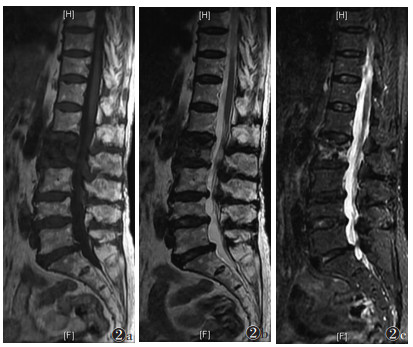

168节椎体中,轻度骨髓水肿32节,中度70节,重度66节。随时间推移,骨髓水肿信号强度逐渐由均匀向非均匀转变,信号范围逐渐减小,边界逐渐清晰;轻度骨髓水肿发生率由8.4%升至50.0%,重度由51.8%降至8.3%,差异均有统计学意义(均P<0.050.05)(表 3)。①Ⅰ期:骨髓水肿比例迅速上升,达到峰值。T1WI、T2WI信号均匀分布,T1WI呈低信号,T2WI和STIR呈高信号,扩散至正常骨髓,呈弥漫性、均匀性、边界不清的形态分布(图 1)。②Ⅱ期:信号分布变得不均匀,水肿范围逐渐受限,并出现点、片状T1WI低信号,T2WI和STIR高信号(图 2)。③Ⅲ期:骨髓水肿较前一期下降,水肿范围局限于骨折区,信号混杂;部分椎体T1WI呈等、低信号,T2WI及STIR呈低、等、高信号(图 3)。④Ⅳ期:骨髓水肿百分比降至最低。T1WI骨折区可见低信号区,边界清晰。T2WI和STIR信号与相邻正常椎体相同(图 4)。

| 图 2 女,75岁,Ⅱ期OVCFs,L2骨折。MRI示明显混合信号,T1WI(图 2a)呈不均匀低信号,T2WI(图 2b)及STIR(图 2c)呈不均匀高信号 |